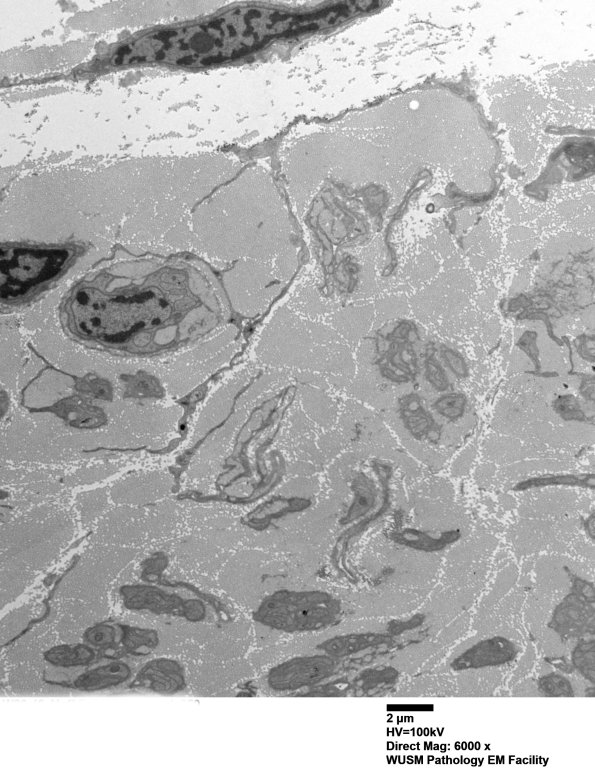

Washington University Experience | PERIPHERAL NEUROPATHY | 4 AXONAL DEGENERATION | 3 Electron Microscopy | 7A5A Chronic Degeneration (Case 33) Sural_050 - Copy

7A5A-C The individual processes in this series of images are hard to establish as Schwannian, fibroblastic or histiocytic. (electron micrographs)